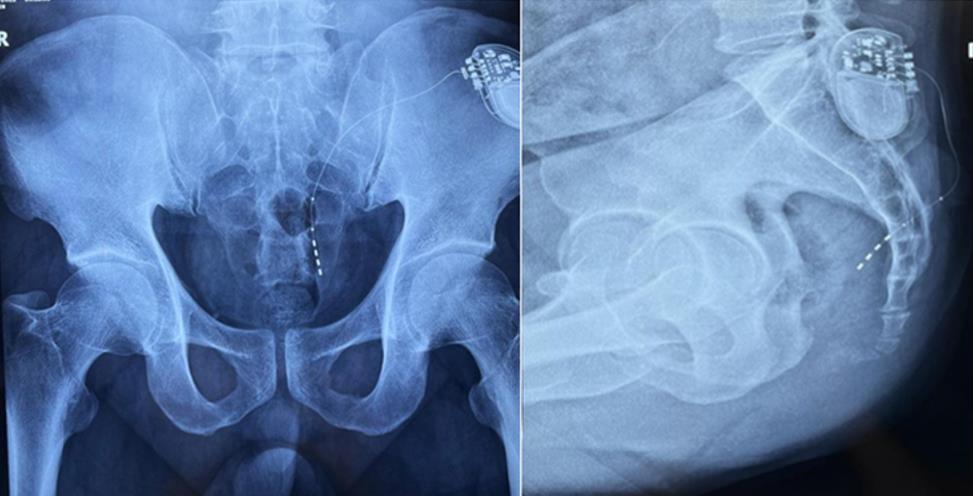

患者術(shù)前影像

大平板一體式移動(dòng)C形臂術(shù)中影像

該患者兩年前被診斷患有膀胱過(guò)度活動(dòng)癥(OAB),出現(xiàn)嚴(yán)重尿頻、尿急、尿細(xì)線等癥狀,醫(yī)生為其做了骶神經(jīng)調(diào)控手術(shù)。近期,患者癥狀又開(kāi)始加重,生活質(zhì)量受到影響,為減輕癥狀,改善生活,患者前往南醫(yī)大二附院就診。衛(wèi)中慶主任及其團(tuán)隊(duì)在查看患者病情后,決定重新調(diào)整電極刺激位置,將刺激點(diǎn)由原左側(cè)骶4神經(jīng)孔改為骶3神經(jīng)孔,通過(guò)新的神經(jīng)調(diào)節(jié)順利地改善了癥狀。

在骶神經(jīng)調(diào)控術(shù)或者骶神經(jīng)刺激術(shù)(SNS)中,醫(yī)師首先會(huì)在透視引導(dǎo)下把電極通過(guò)導(dǎo)針插入到骶3神經(jīng)孔位置,通過(guò)脈沖電流的刺激,達(dá)到興奮神經(jīng)纖維并抑制逼尿肌收縮。在這一步,醫(yī)師會(huì)先對(duì)患者的神經(jīng)刺激反應(yīng)做測(cè)試評(píng)估,如果刺激效果明顯,說(shuō)明該方案能夠達(dá)到手術(shù)預(yù)期。接下來(lái)醫(yī)師會(huì)在附近皮下脂肪處植入一塊脈沖電流發(fā)生器并與電極相連,使該部位今后能得到長(zhǎng)期的電刺激,改善OAB癥狀。